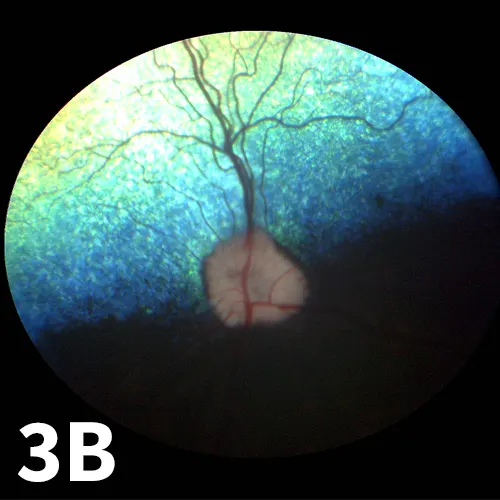

Figure 3A Fundus picture of left eye of a 6-year-old dachshund. The optic disc is atrophied. Compare to Figure 2, in which both the retina and optic disc are atrophied, and to the normal right eye (3B).